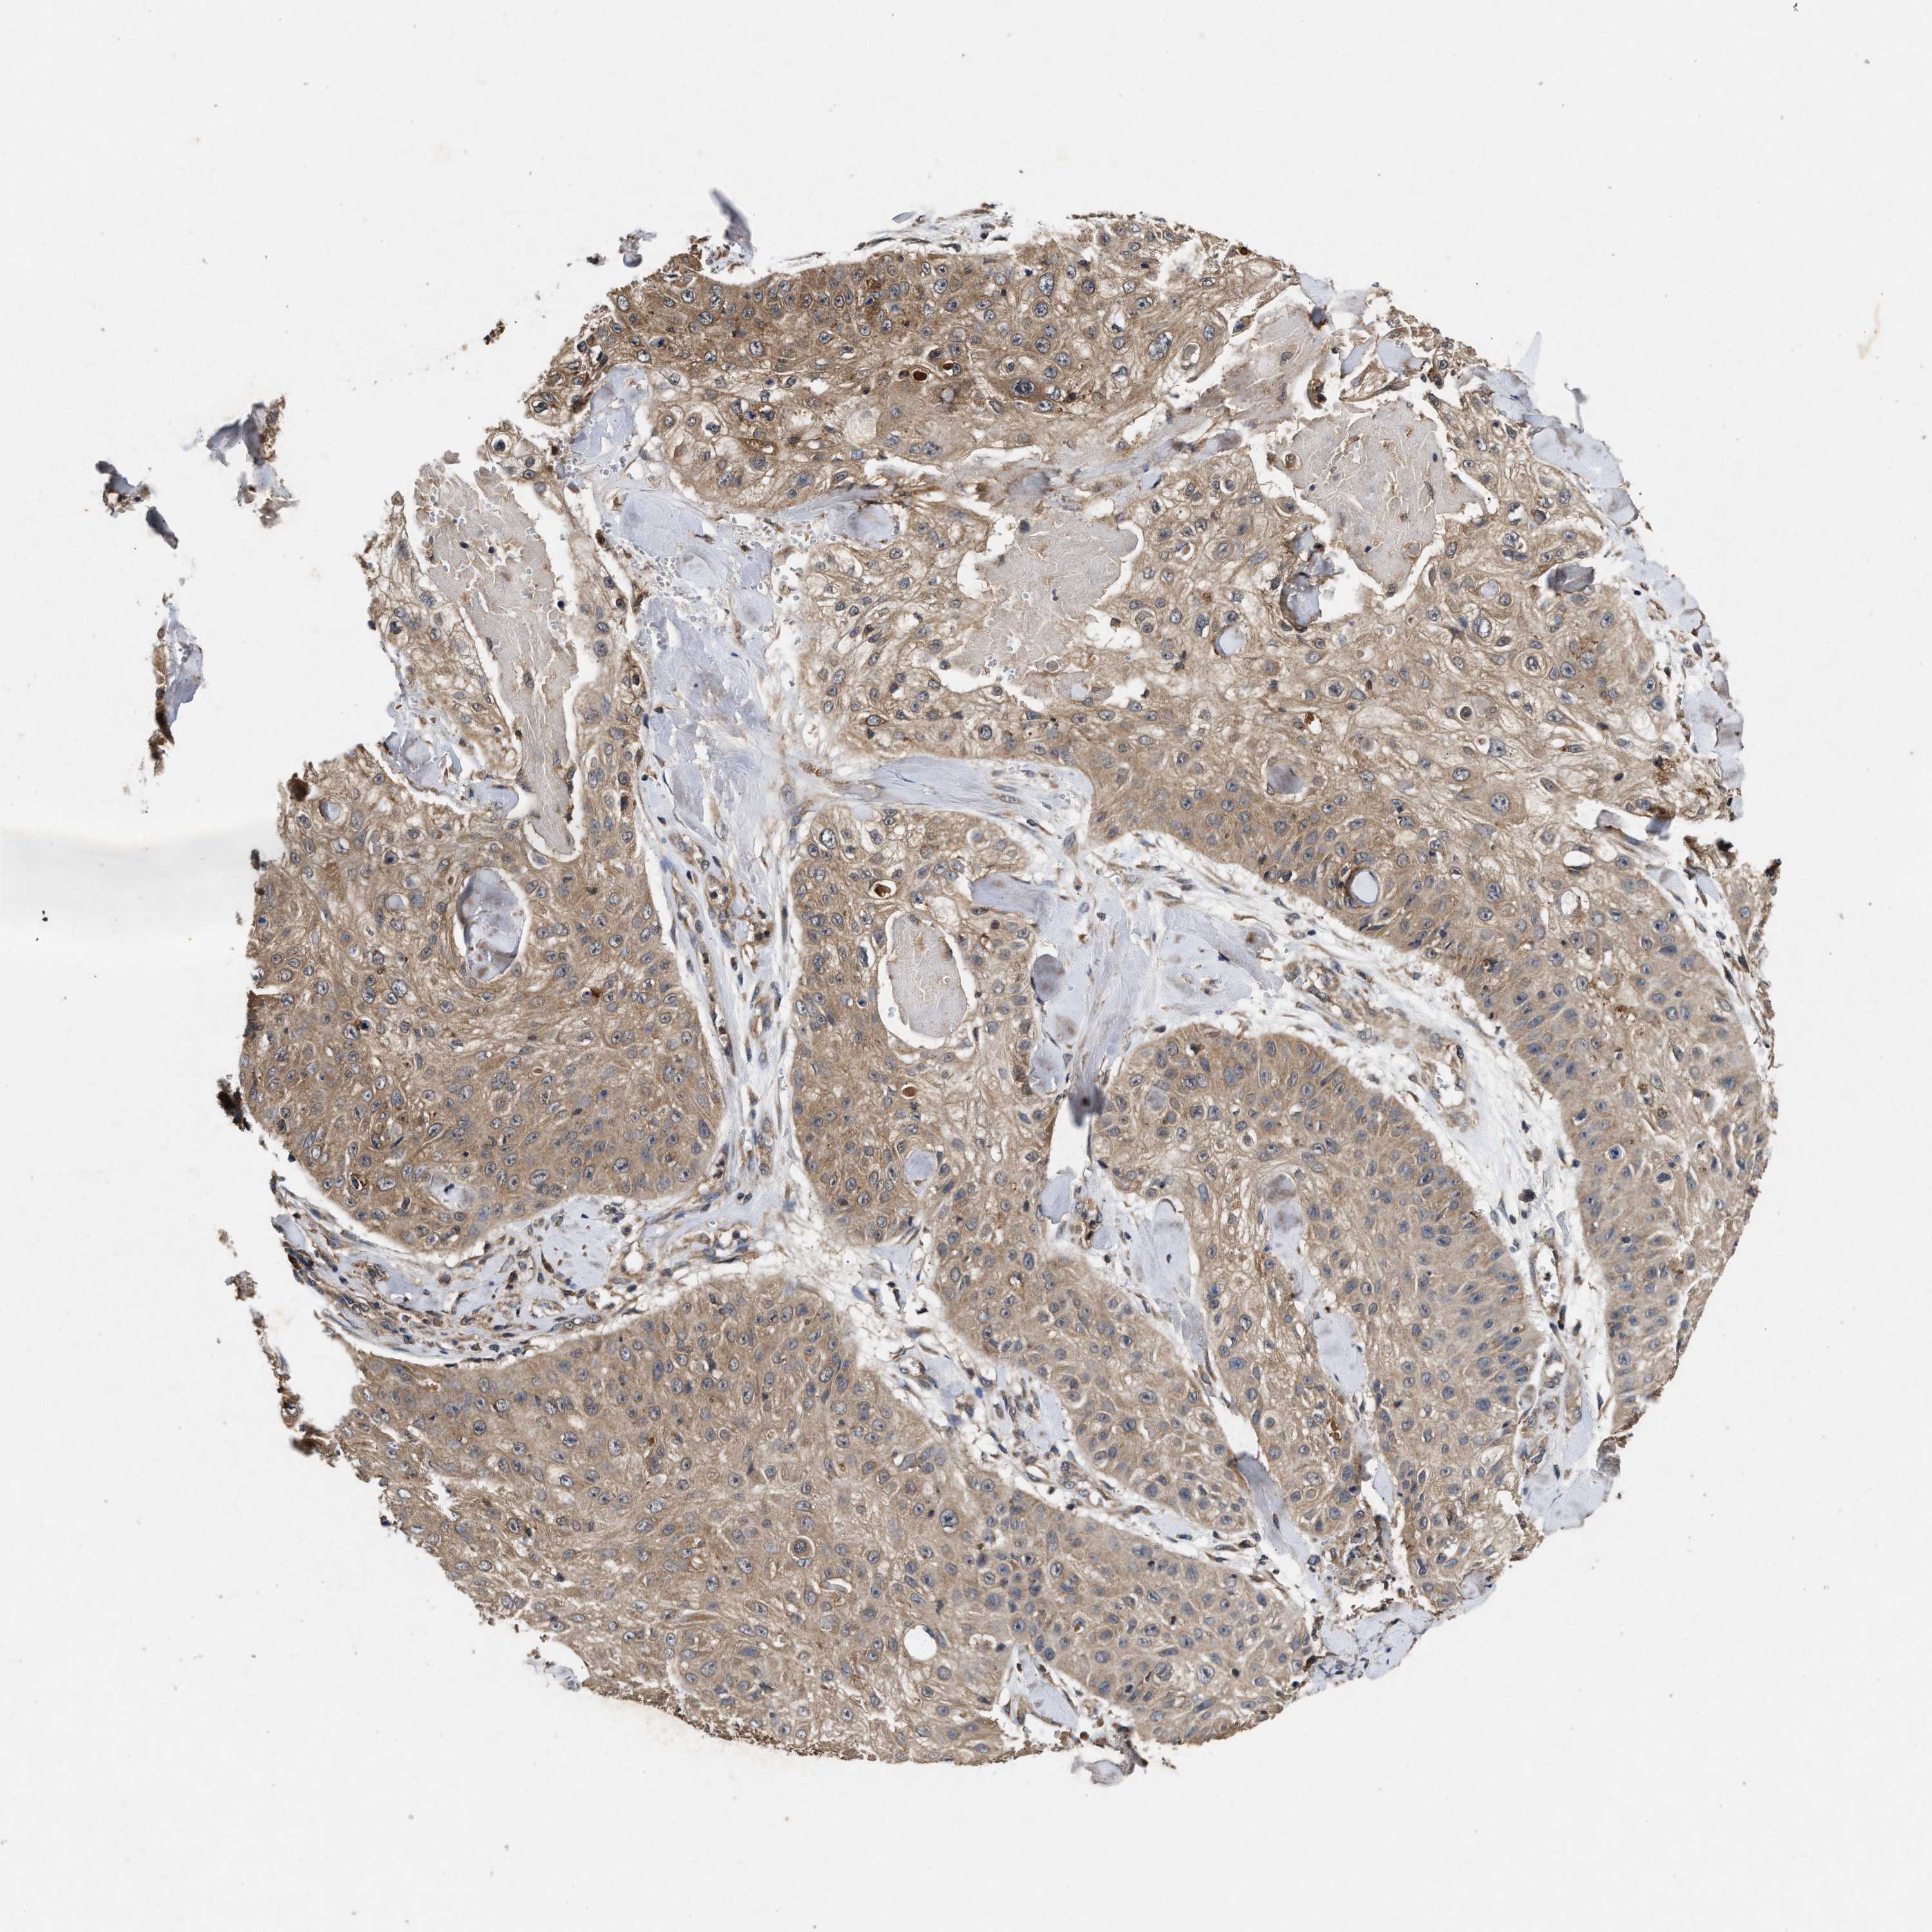

SKIN CANCER - Protein expressioni

A mouse-over function shows sample information and annotation data. Click on an image to view it in a full screen mode. Samples can be filtered based on level of antibody staining by selecting one or several of the following categories: high, medium, low and not detected. The assay and annotation is described here.

Antibody staining in the annotated cell types in the current human tissue is reported as not detected, low, medium, or high, based on conventional immunohistochemistry profiling in selected tissues. This score is based on the combination of the staining intensity and fraction of stained cells.

Each image is clickable and will lead to virtual microscopy that enables deeper exploration of all samples and also displays staining intensity scores, fraction scores and subcellular localization as well as patient and tissue information for each sample.

Antibody HPA050294

Basal cell carcinoma